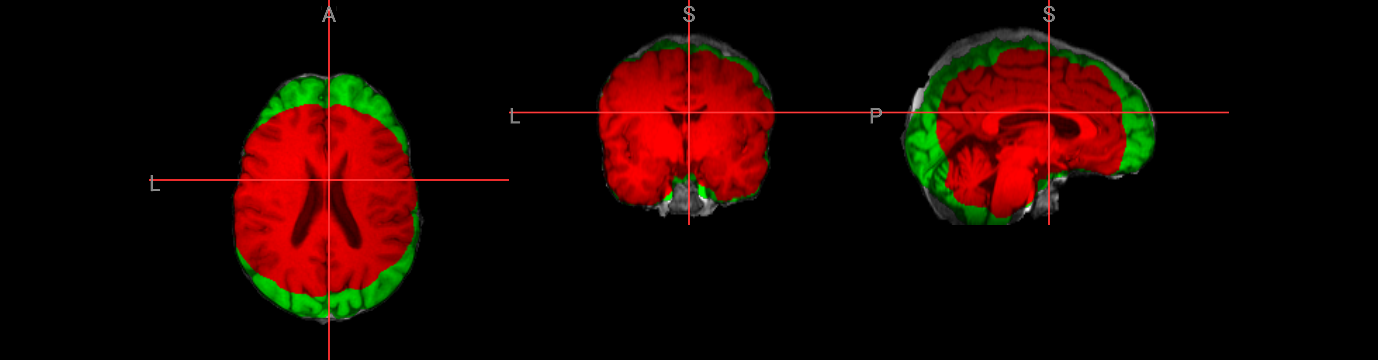

nv.load_volumes( [{"path": "./fsl_course_data/intro/structural.nii.gz", "colormap": "gray"},

{"path": "./output/structural_brain.nii.gz", "colormap": "red" },

{"path": "./output/structural_brain_skull.nii.gz", "colormap": "blue" }])

nv

Image(url='https://raw.githubusercontent.com/NeuroDesk/example-notebooks/refs/heads/main/books/images/fsl_course_bet05.png')